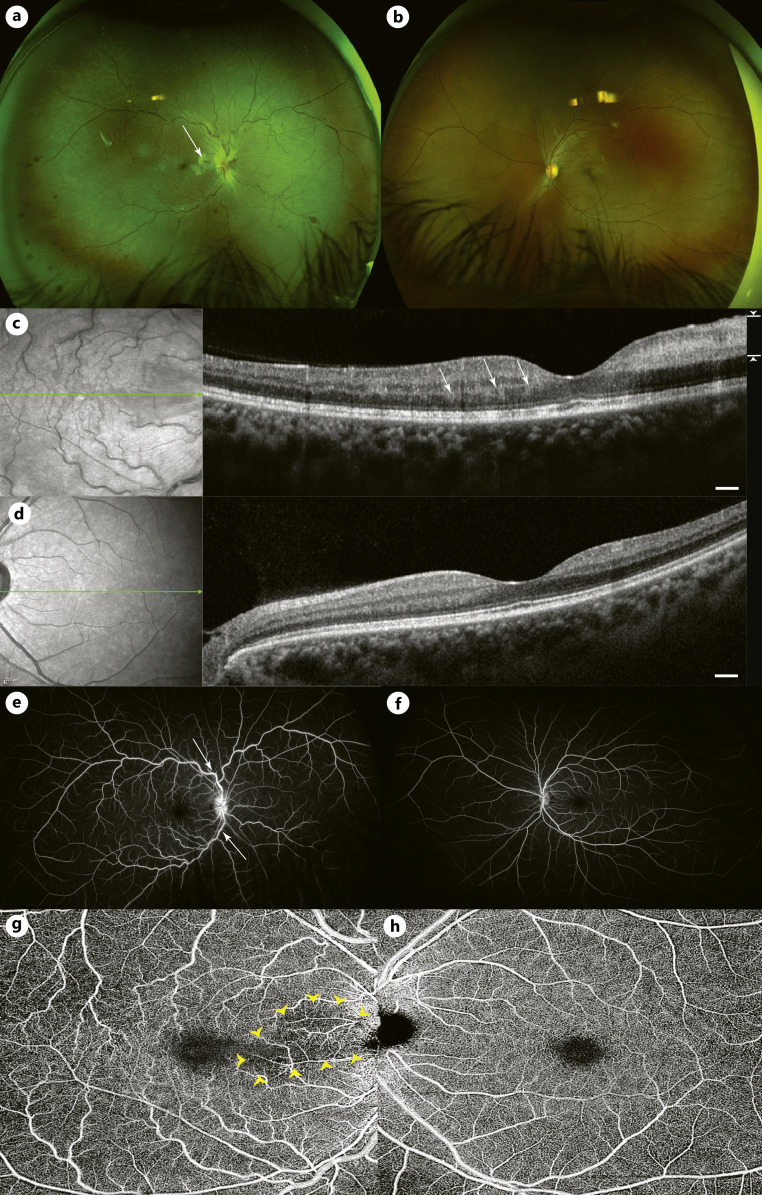

简介:局部曲安奈德是一种广泛用于瘢痕性皮肤疾病(如瘢痕疙瘩)的治疗方法,已知如果在眼周区域使用曲安奈德会导致视网膜血管并发症。病例介绍:一名32岁女性因瘢痕瘤毁损,在右耳垂注射曲安奈德皮质类固醇(TAC)后,右眼出现突发性短暂性视力下降和迟发性缓慢消退的视力丧失。临床表现为视网膜分支动脉闭塞并伴有视网膜中央静脉闭塞。进入视网膜循环的TAC颗粒与视网膜分支动脉的血栓栓塞闭塞和随后的视网膜中央静脉阻塞有关。结论:该病例应提醒临床医生,由于颈外动脉和颈内动脉循环之间有丰富的吻合,在头面区域注射皮质类固醇总是存在视网膜血管闭塞的潜在危险。

Case presentation: A 32-year-old female experienced a prompt onset transient vision decrease and a delayed onset, slow-resolving vison loss in the right eye (OD) following the last of a series of triamcinolone acetonide corticosteroid (TAC) injections in her right earlobe for a disfiguring keloid. Clinically, she developed a branch retinal arterial occlusion accompanied by features of a central retinal vein occlusion. The TAC particles that entered the retinal circulation are implicated in the thrombo-embolic occlusion of the branch retinal artery and subsequent blockage of the central retinal vein.